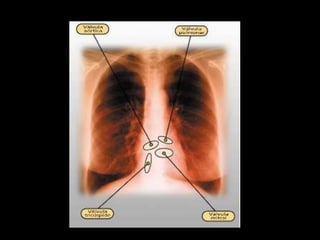

CORAZÓN: SITUACIÓN Y CARACTERÍSTICAS

• Órgano de paredes musculosas

• Situado entre los dos pulmones, detrás y

levemente a la izquierda del esternón

• Tamaño un poco mayor que un puño

• Peso de unos 250 g.

• Vértice inclinado hacia la izquierda de la caja

torácica.

• El músculo cardíaco (MIOCARDIO)

-

externamente envuelto por una especie de

saco, de paredes dobles (PERICARDIO)

Internamente, sus cavidades internas,

revestidas por tejido endotelial llamado

(ENDOCARDIO)

ÁREA PRECORDIAL

• A: 2° espacio I.D.

2 cm.

• B: 5° espacio I.D.

2 cm

• C: 2° espacio I.I.

• D: 5° espacio I.I.

8-10 cm

A-D : 12-13 cm.

B-C : 10-11 cm.

A

B

C

D